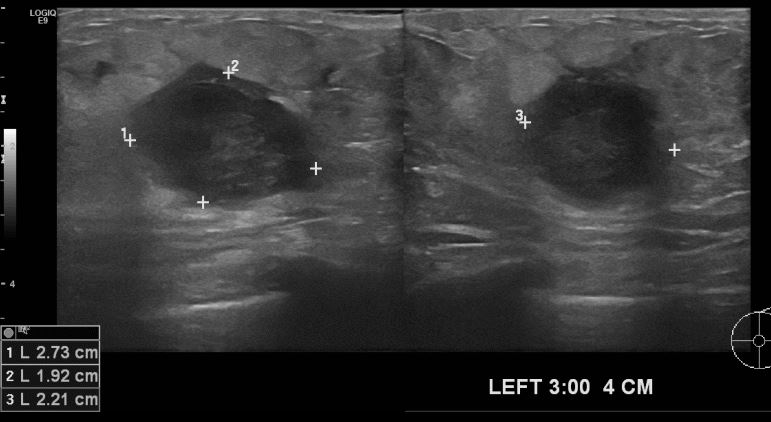

좌측유방 통증과 멍울 있어 내원하신 68세 여자환자분으로 초음파시행후 좌측유방에

의심스런 멍울을 중심핵생검 실시하여 침윤성 유관암 진단되셨습니다.